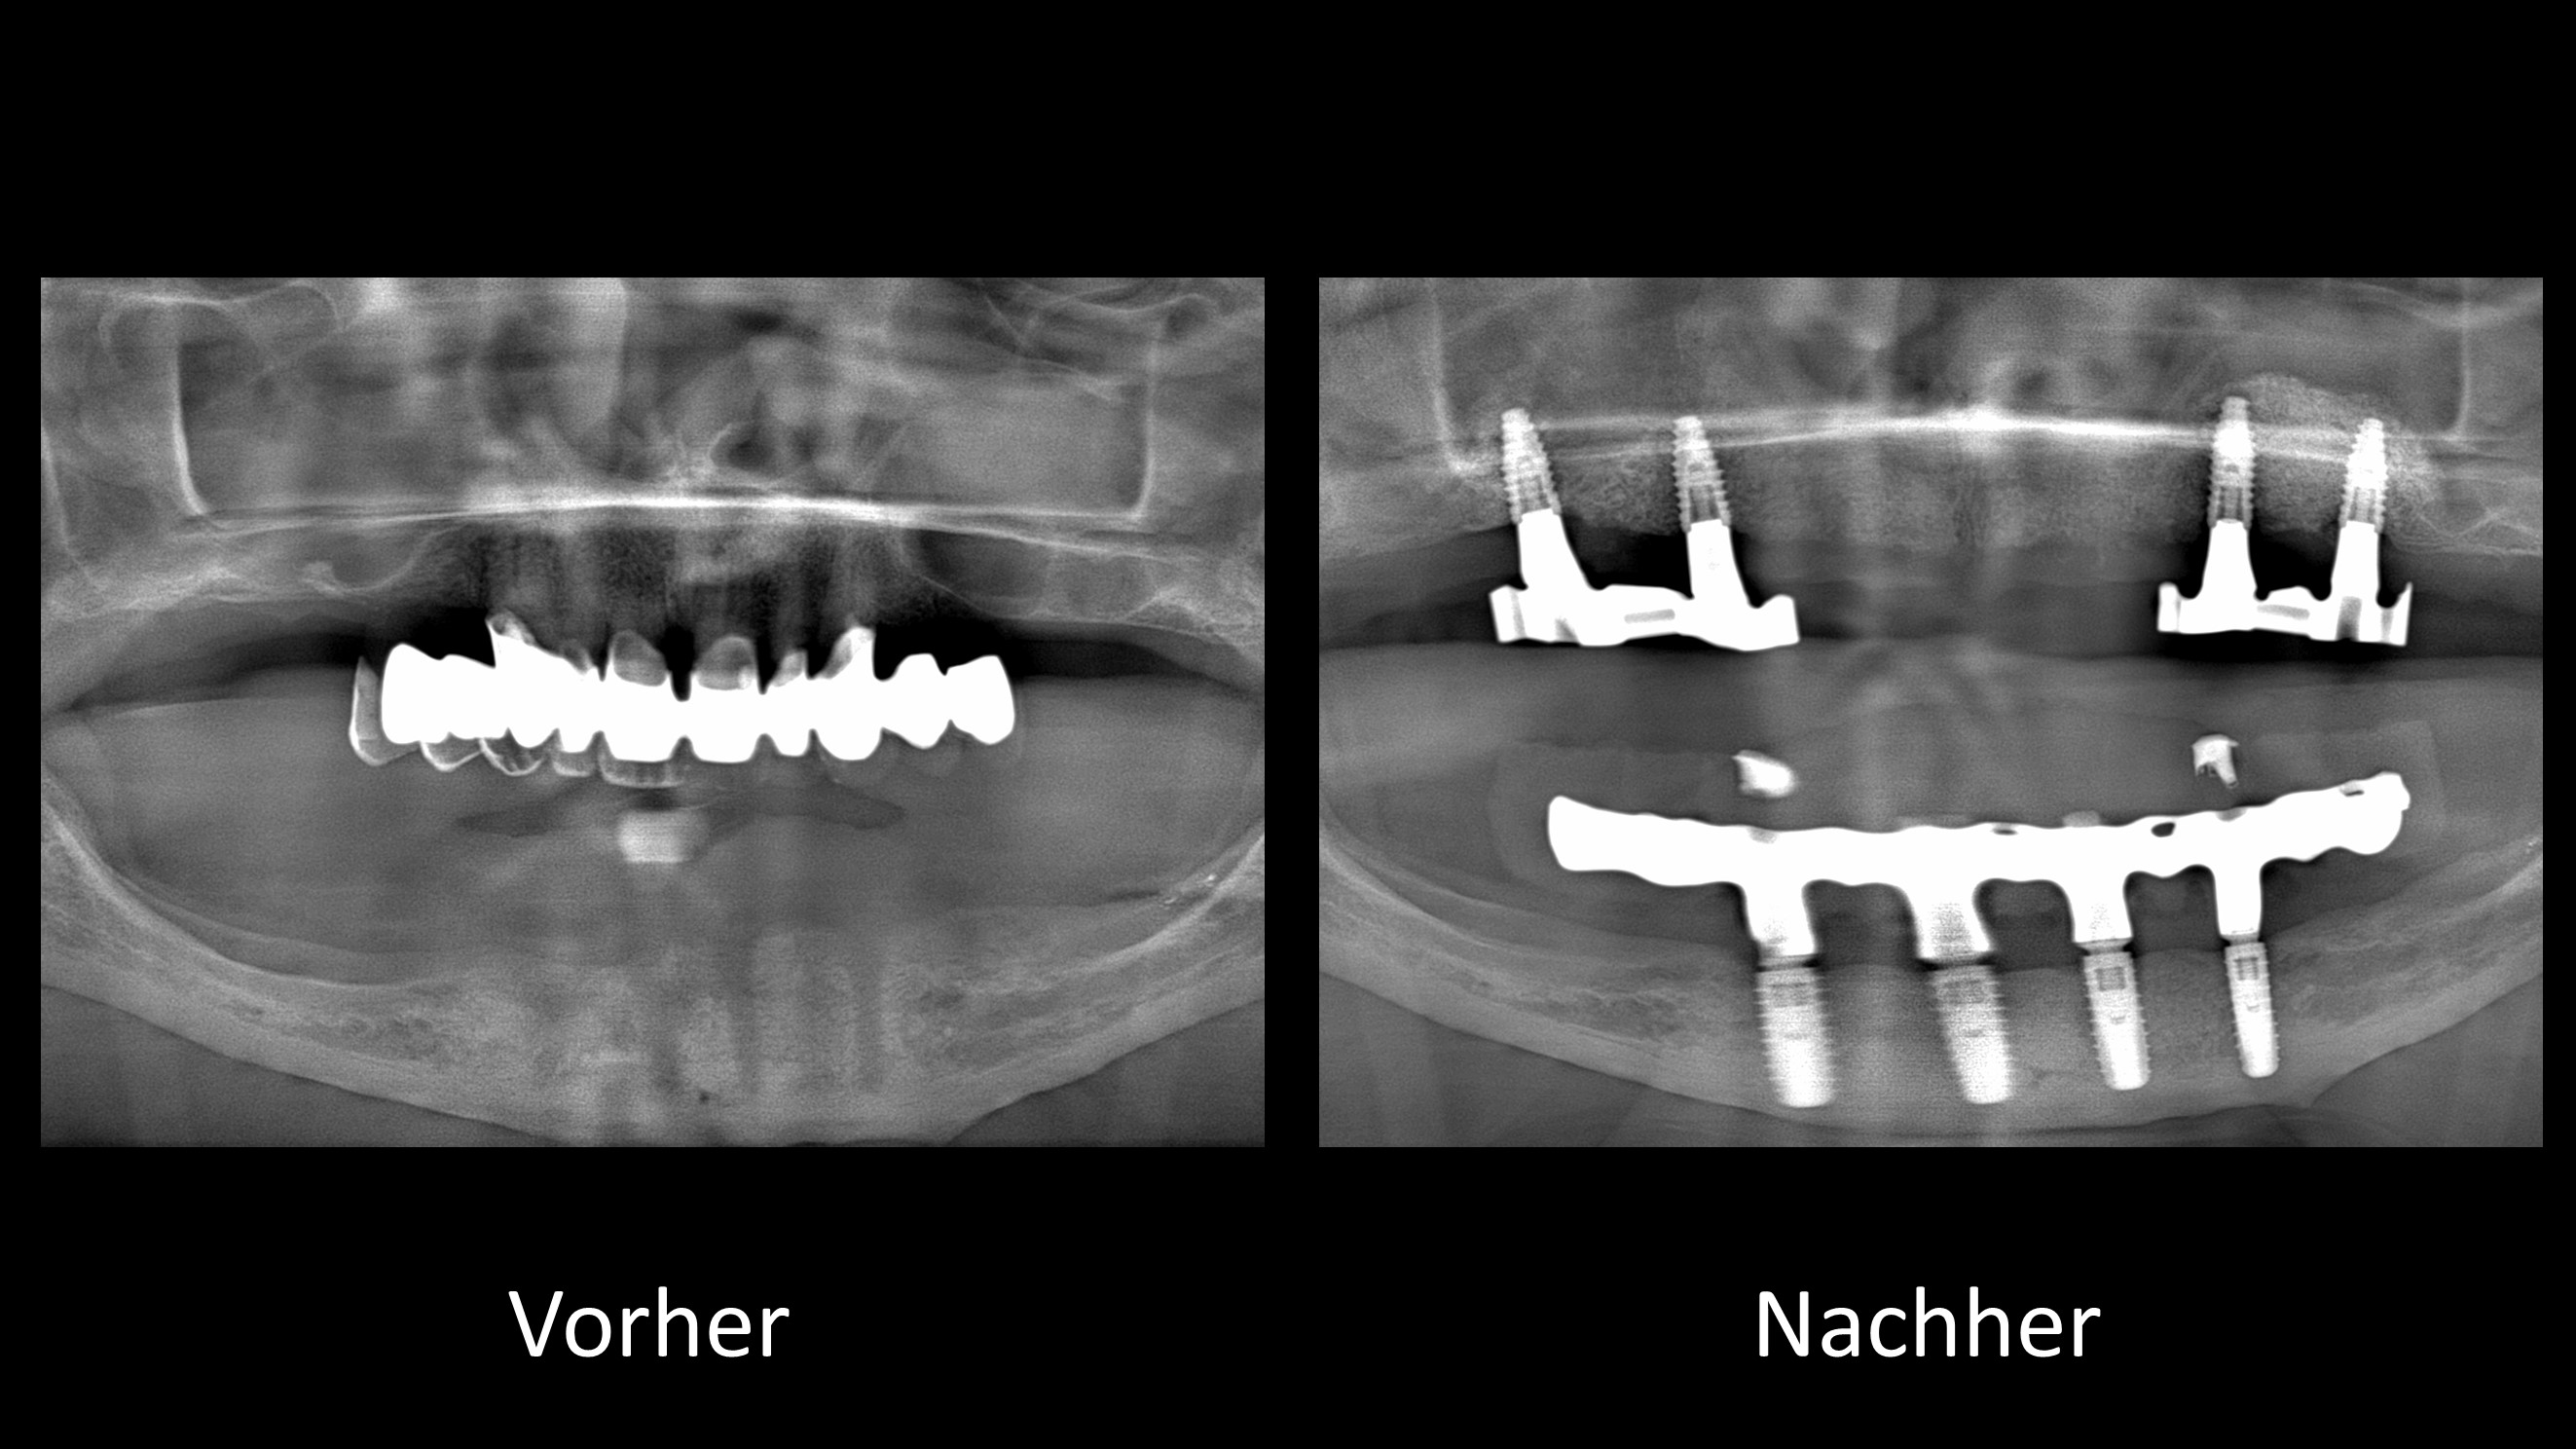

Vorher-Nachher-Röntgenbilder:

Ganzkiefer-Brücken auf 4 und mehr Implantaten

Bei unserer Sofortimplantat-Methode werden die hinteren Implantate meist schräg eingesetzt

und sofort mit den neuen Zähnen versorgt:

Durch die Schrägstellung sind einerseits längere Implantate möglich und andererseits werden gleichzeitig anatomisch wichtige Strukturen geschont (Unterkiefernerv, Kieferhöhle). Zusätzlich resultiert die Schrägstellung in einer statisch günstigeren Belastung und einer besseren Verteilung der Implantate (weiter hinten im Kiefer).